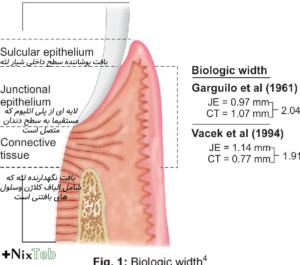

اگر پوسیدگی به زیر لثه برسد، ترمیم یا روکش نمیتواند بهدرستی قرار گیرد و لثه دچار التهاب دائمی میشود.

برای قرارگیری سالم ترمیم، حداقل ۲–۳ میلیمتر فاصله از استخوان لازم است. اگر پوسیدگی بیش از حد پایین باشد، حتی جراحی هم کمکی نمیکند و کشیدن دندان ضروری میشود.